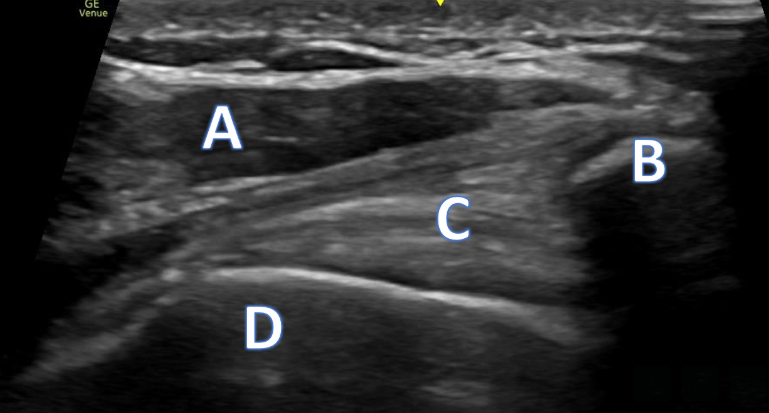

A 66-year-old male with right anterior elbow pain, ecchymosis, and a “lump” in his right upper extremity after a ground level fall.